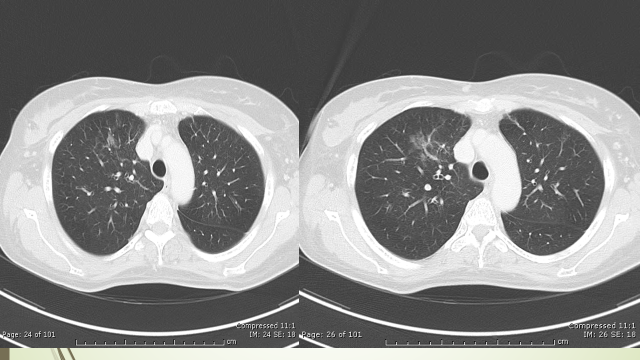

During the course, despite the ongoing treatment, she developed recurrent junctional tachycardia and worsening of respiration due to ILD. Chest X-ray showed bilateral lung infiltrates. CT chest showed patchy ground glass opacification with interlobular septal thickening in bilateral peri-hilar lung parenchyma with multiple osteolytic lesions in vertebrae and sternum [figure 1].

CT chest showed significant improvement [figure 7].